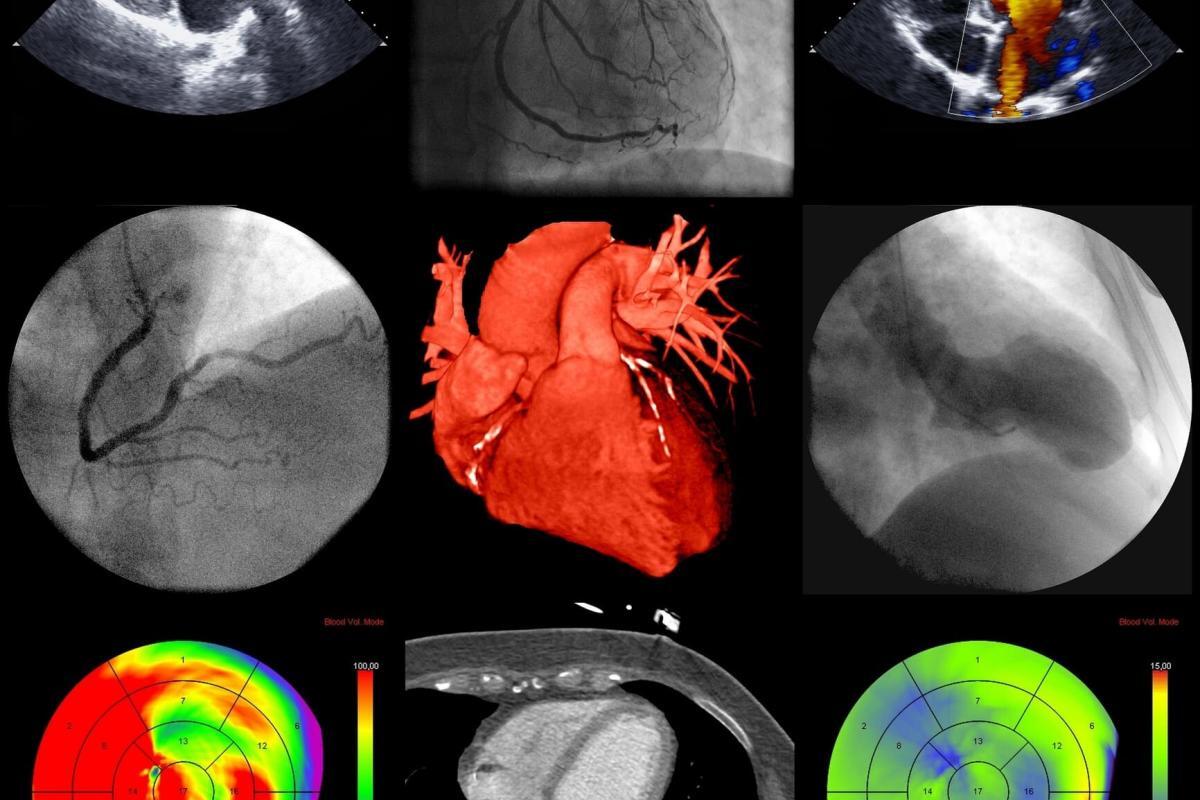

Various imaging techniques are employed to capture the distribution of radiopharmaceuticals within the heart, each offering distinct advantages:

- Single Photon Emission Computed Tomography (SPECT): SPECT imaging involves the use of gamma cameras to detect the radiation emitted by radiopharmaceuticals. It provides three-dimensional images of myocardial perfusion and is widely used for diagnosing coronary artery disease.

- Positron Emission Tomography (PET): PET imaging uses radiopharmaceuticals like F-18 FDG and N-13 ammonia to produce high-resolution images of metabolic and perfusion processes in the heart. PET is particularly valuable for assessing myocardial viability and detecting hibernating myocardium.

- Planar Scintigraphy: This older technique involves capturing two-dimensional images of radiopharmaceutical distribution. While less commonly used today, it can still be useful in specific diagnostic scenarios.

- Evaluation of Myocardial Perfusion: Both SPECT and PET imaging are used to assess myocardial perfusion, providing detailed maps of blood flow distribution within the heart. This evaluation is vital for diagnosing and managing various cardiac conditions.